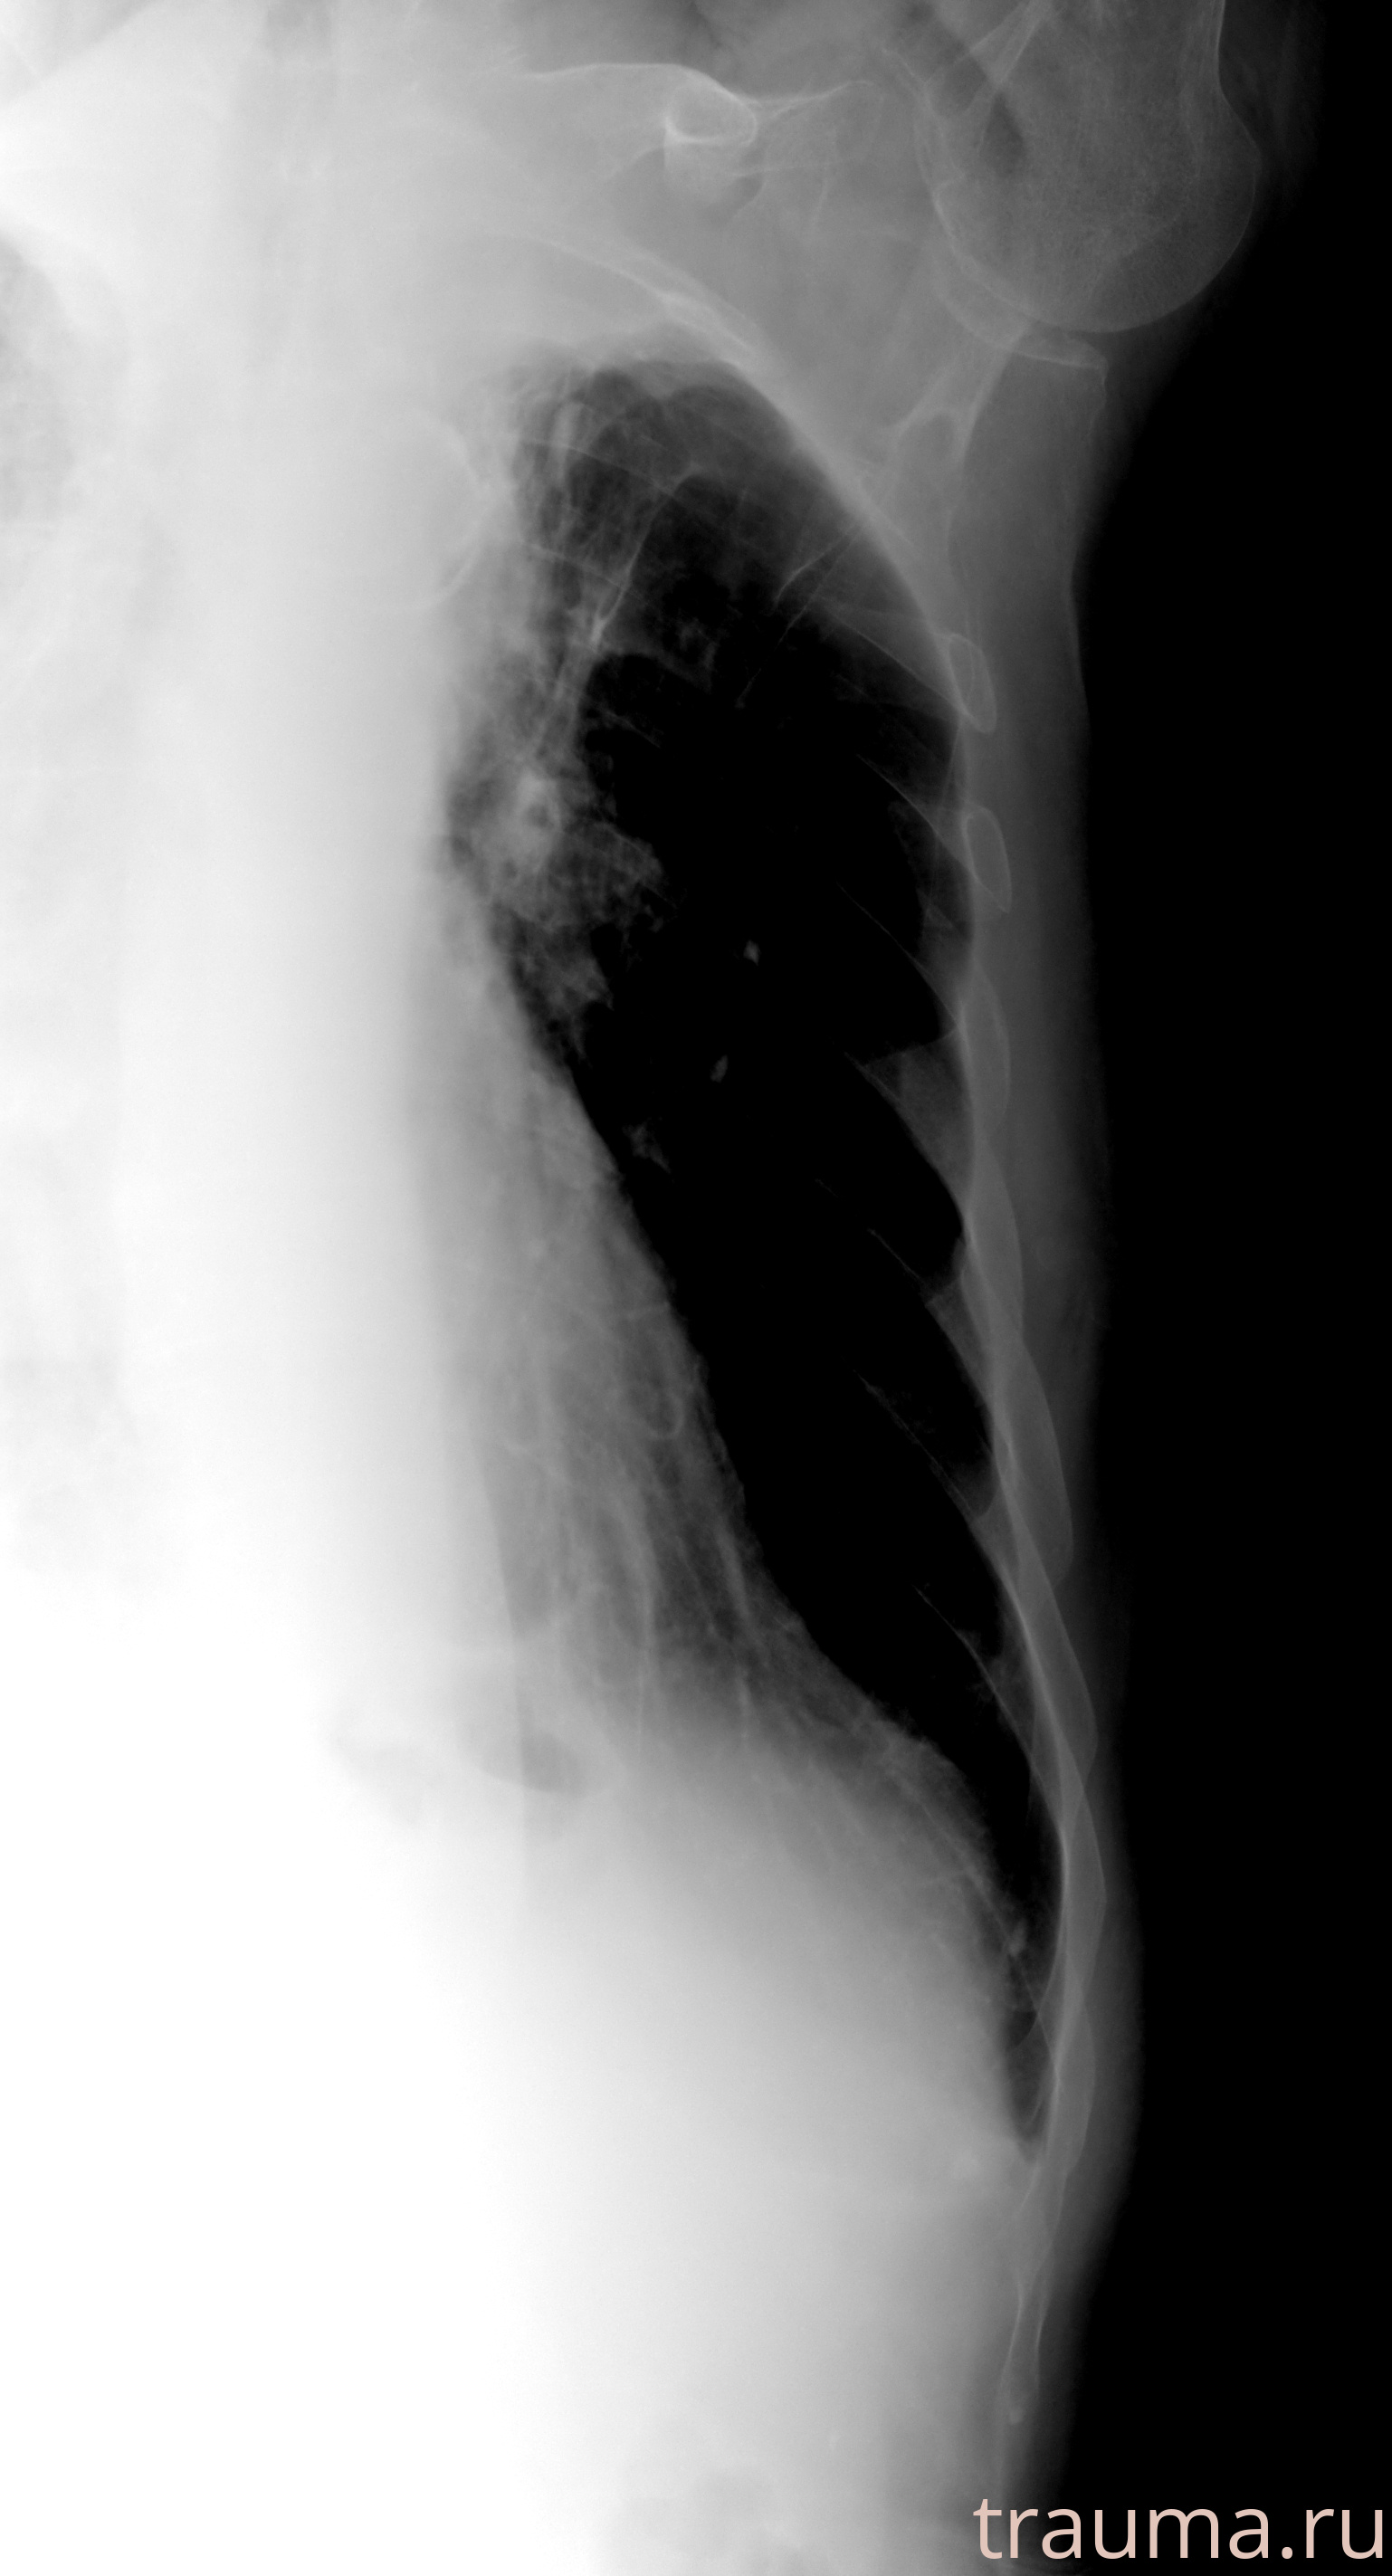

Рентгенограммы

Рентген на дому: по вашему адресу приезжает врач-рентгенолог, травматолог-ортопед с мобильным рентгеновским аппаратом, проводит диагностику травмы или заболевания, делает необходимые рентгенограммы, дает рекомендации по дальнейшему лечению. Получить качественные снимки в домашних условиях возможно благодаря уникальной методике, разработанной МосРентген Центром для института  Склифосовского

при переломе шейки бедра и пневмонии от компании МосРентген Центр - партнера Института имени Склифосовского